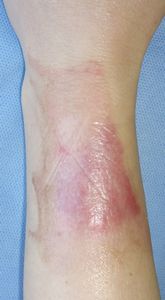

42歳女。

2016年11月6日,職場(身障者施設)でお粥の釜を持ち上げたところ,汁がはねて左前腕に熱傷受傷。帰宅後,ネットで調べてラップで覆ったところ痛みはなくなった。

10日,一度診てほしいとのことで当科を受診。ハイドロコロイド被覆材で治療。

| 11月10日 | 11月15日 | 11月18日 | 11月22日 |